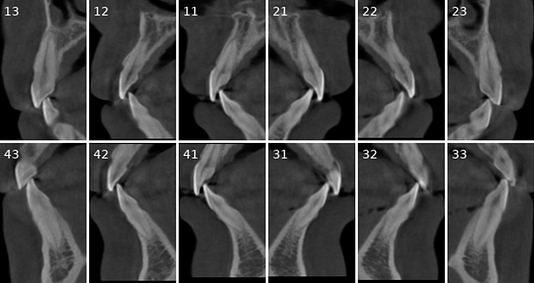

Cross-sectional and coronal views of teeth show torque and buccolingual relationships such as crossbite.

Tooth number is selected to analyze the root canal morphology within the CBCT radiograph.

Sagittal and coronal slices and highlighting the angle/curvature/length of the canals.